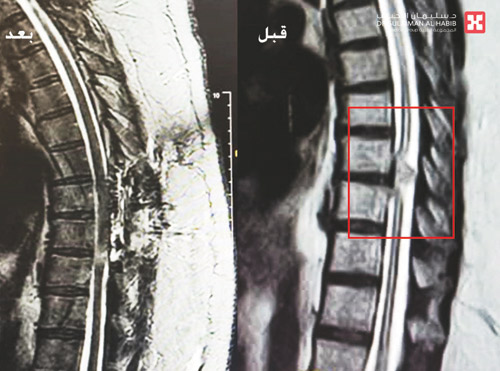

نجح مستشفى الدكتور سليمان الحبيب بالقصيم بفضل من الله تعالى في إجراء عملية جراحية دقيقة ومعقدة بالعمود الفقري لإعادة قدرة المشي والحركة لمريضة في العقد الرابع من العمر، ذكر ذلك الدكتور ناجي مسعود استشاري جراحة المخ والأعصاب والعمود الفقري رئيس الفريق الطبي المعالج. وأضاف أن المريضة وصلت إلى المستشفى على كرسي متحرك وتبين أنها فقدت القدرة على المشي منذ 3 أشهر وتعاني من احتباس شديد بالمثانة. وقد كشفت الفحوصات وجود ورم في الظهر بالفقرات الصدرية الثامنة والتاسعة يسبب ضغطاً شديداً على منطقة النخاع الشوكي مما نتج عنه الأعراض الحادة التي تعاني منها المريضة. وذكر أن الفريق المعالج قرر سرعة التدخل الجراحي لإزالة الورم وللحد من المضاعفات التي قد تصيب المريضة لاحقاً والتي من أبرزها الشلل الدائم للأطراف السفلية. وقد أجريت للمريضة عملية جراحية استمرت 4 ساعات تم خلالها عمل فتحة بالفقرات الصدرية في الظهر بطول 3-4 سم للوصول إلى مكان الورم وتم تحريره من الحبل الشوكي ومن ثم استئصاله بالكامل. وأضاف الدكتور ناجي أن العملية تكللت بالنجاح دون أية مضاعفات واستطاعت المريضة المشي في اليوم الخامس بمفردها ولله الحمد دون مساعدة، وخرجت إلى منزلها في اليوم السابع وهي بصحة جيدة.